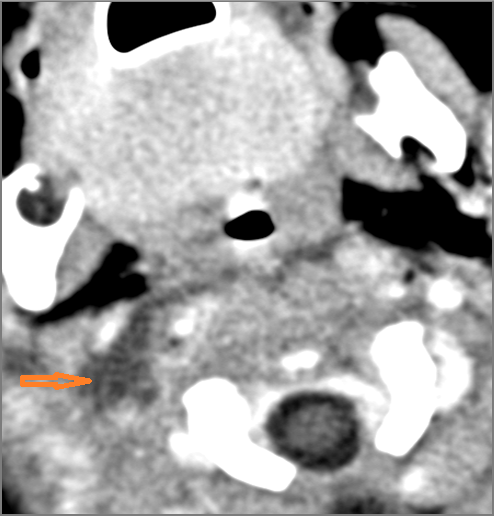

There is abscess at the periphery of the lymphoid tissue of the palatine tonsil within the potential peritonsillar space.

If there is suppurative cervical adenopathy the purulent material outside the lymph node(s) capsule(s).